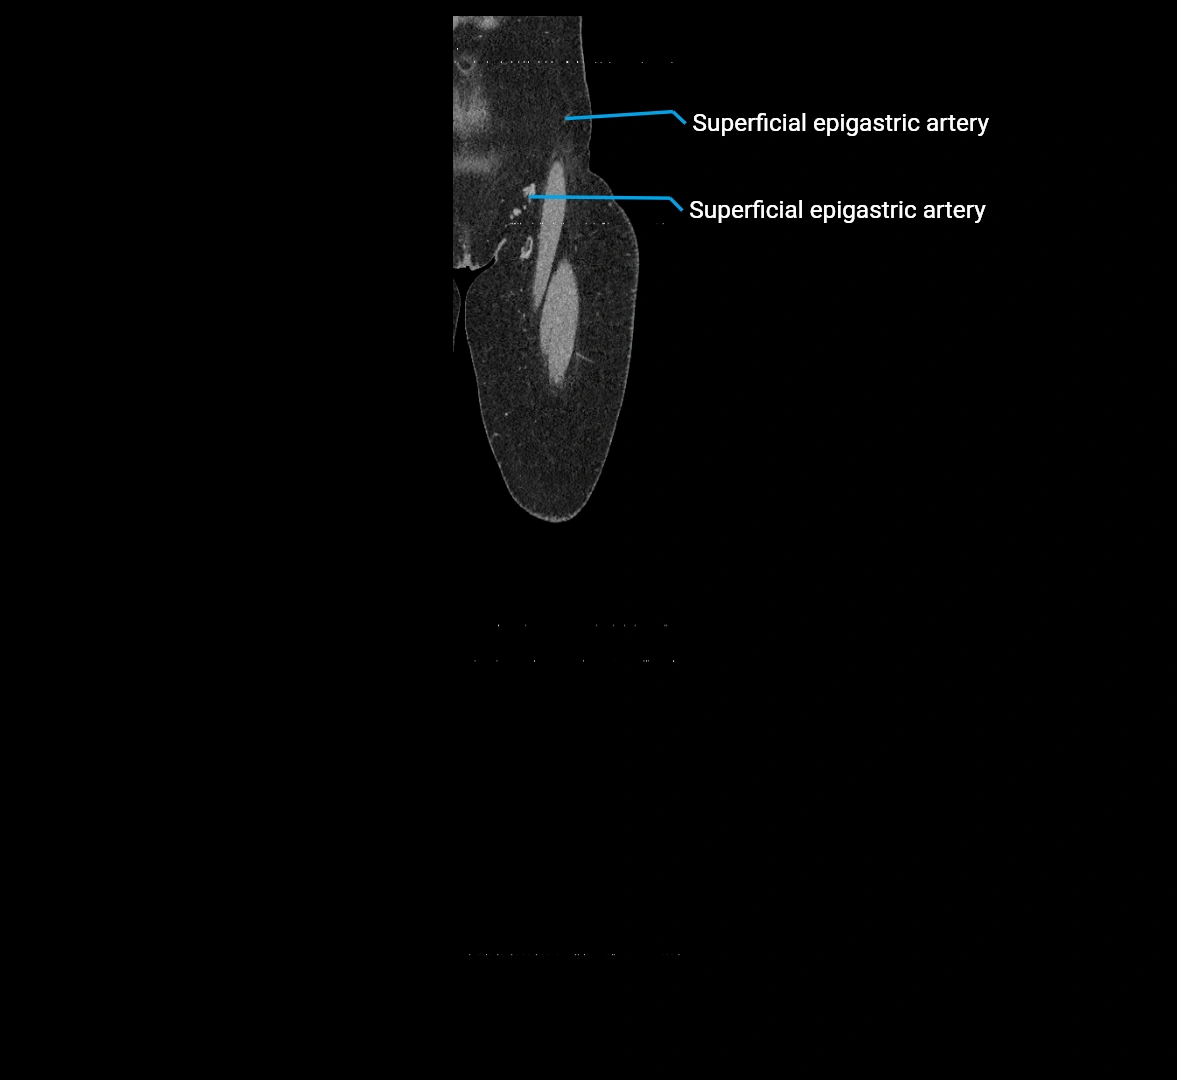

MRI images

image